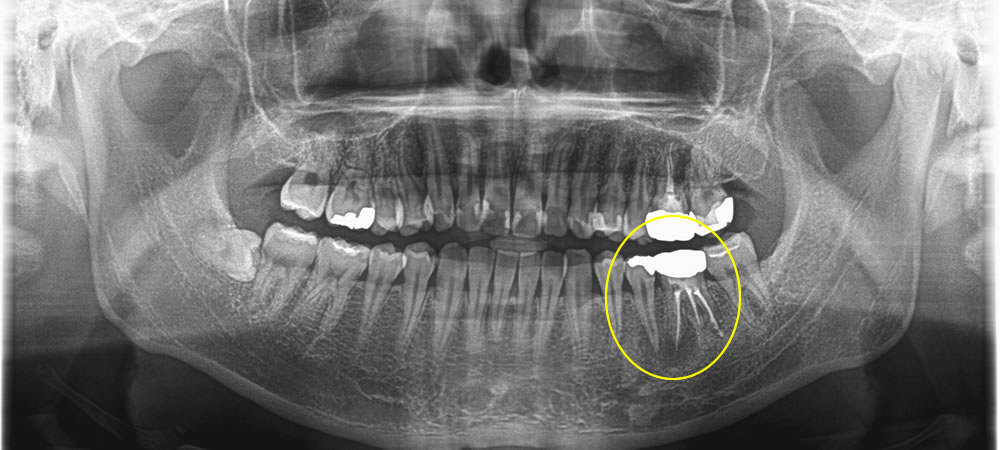

歯根に膿が溜まった歯を抜歯してインプラントで治療した症例

こちらは、左下奥から2番目の歯が噛むと痛みがあるとのことで来院された患者さまです。

レントゲン検査の結果、過去に他院で治療された第一大臼歯の歯の根っこに膿が溜まっていることが確認できました。

CT写真撮影にて精密検査を行ったところ膿がかなり大きく、手前の歯まで骨の損傷が大きかったため、治療をするとなると2本とも残すことは難しいと診断しました。患者さまと相談し、当該歯を抜歯後にインプラントで治療する計画を立てました。